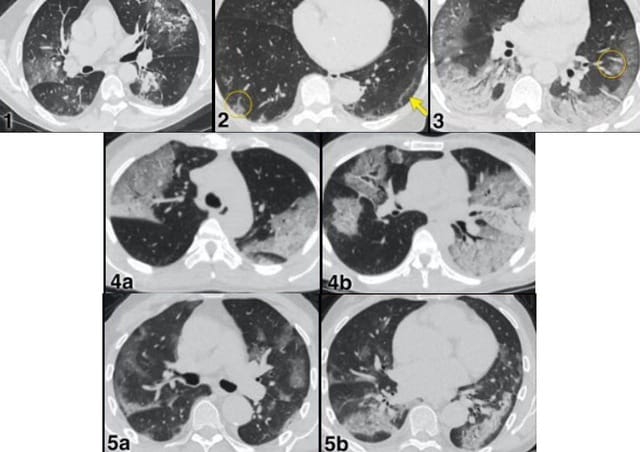

Một trường hợp được báo cáo là bé gái 15 tuổi (ở Bắc Ninh), vào viện trong tình trạng sốc, hôn mê, suy hô hấp. Kết quả chụp CT cho thấy phù não, hình ảnh tổn thương lan tỏa ở phổi. Cấy máu dương tính với tụ cầu vàng. Bệnh nhân may mắn được cứu sống sau nhiều ngày hồi sức tích cực.

- Chụp X-quang phổi, CT sọ não nếu nghi tổn thương tạng.